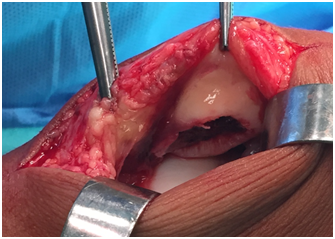

Due to the fragment characteristics (dimensions and location), surgical treatment was the option. In the same day, the child was operated: a medial parapatellar approach was chosen (Figure 3).

Figure 3 Medial parapatellar approach of the right knee, showing a large void beginning at the inferior pole of the patella, with extension to both facets, mostly the medial one.